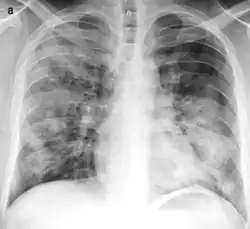

Bronchopneumonia

Bronchopneumonia is a subtype of pneumonia. It is the acute inflammation of the bronchi, accompanied by inflamed patches in the nearby lobules of the lungs.[1]

It is often contrasted with lobar pneumonia; but, in clinical practice, the types are difficult to apply, as the patterns usually overlap.[2] Bronchopneumonia (lobular) often leads to lobar pneumonia as the infection progresses. The same organism may cause one type of pneumonia in one patient, and another in a different patient.

On gross pathology there are typically multiple foci of consolidation present in the basal lobes of the human lung, often bilateral. These lesions are 2–4 cm in diameter, grey-yellow, dry, often centered on a bronchiole, poorly delimited, and with the tendency to confluence, especially in children.